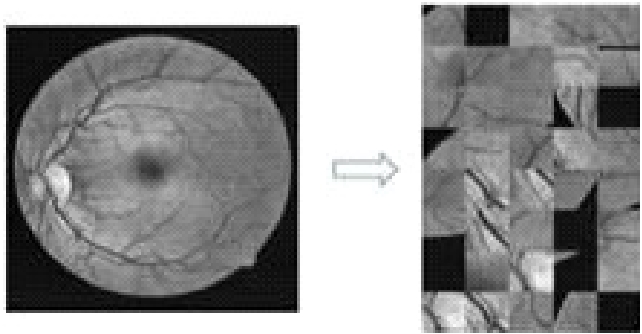

由于眼底血管结构复杂多变,且图像中血管与背景对比度低,眼底血管分割存在巨大困难,尤其是微小型血管难以分割。基于深层全卷积神经网络的U-Net能够有效提取血管图像全局及局部信息,但由于其输出为灰度图像,并采用硬阈值实现二值化,这会导致血管区域丢失、血管过细等问题。针对这些问题,提出一种结合U-Net与脉冲耦合神经网络(PCNN)各自优势的眼底血管分割方法。首先使用迭代式U-Net模型凸显血管,即将U-Net模型初次提取的特征与原图融合的结果再次输入改进的U-Net模型进行血管增强;然后,将U-Net输出结果视为灰度图像,利用自适应阈值PCNN对其进行精准血管分割;在U-Net模型中引入Batch Normalization和Dropout,提高训练速度,有效缓解过拟合问题。实验结果表明,所提方法的AUC在DRVIE、STARE和CHASE_DB1数据集上分别为0.979 6,0.980 9和0.982 7。该方法可以提取更多的血管细节,且具有较强的泛化能力和良好的应用前景。